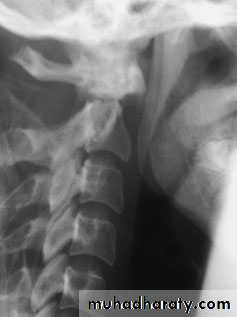

Cervical Spine X-RayLateral radiograph

A/P radiographThoracic Anatomy

CERVICAL SPINE INJURIES

The patient will usually give a history of a fall from a height, a diving accident or a vehicle accident in which the neck is forcibly moved. In a patient unconscious from a head injury, a fractured cervical spine should be assumed (and acted upon) until proved otherwise.An abnormal position of the neck is suggestive, and careful palpation may elicit tenderness.